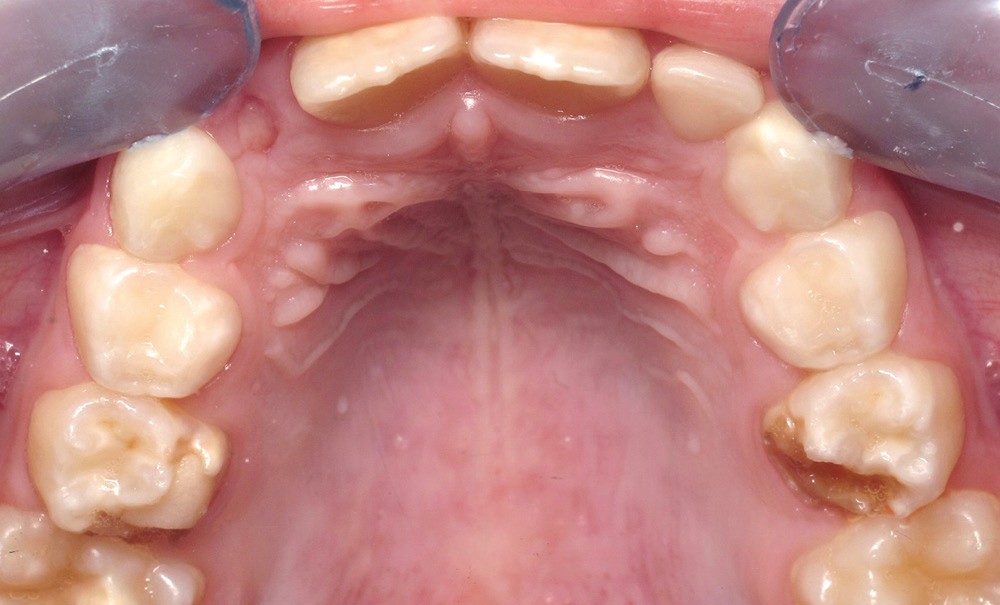

Les anomalies de structure amélaire peuvent avoir des répercussions fonctionnelles, esthétiques et psychologiques majeures dès la petite enfance. La prise en charge des patients doit être précoce et doit s’appuyer sur des approches restauratrices fixées. D’apparition récente, les coiffes pédiatriques en zircone (CPPz) sont une option thérapeutique pour le traitement des anomalies de structure de l’émail, bien qu’elles ne fassent pas encore partie des recommandations. Le traitement des patients présentant une anomalie de structure amélaire peut être complexe, selon l’ampleur de l’atteinte et le nombre de dents à restaurer. Une optimisation et une adaptation des principes de mise en œuvre des CPPz sont utiles. Au travers de cas cliniques, nous illustrerons le traitement d’enfants présentant des anomalies de structure de l’émail à l’aide de CPPz, du cas simple au cas complexe, de la pose au suivi des restaurations.

Les anomalies de structure des dents temporaires se manifestent par des atteintes très diverses : des anomalies de teinte, de morphologie, d’état de surface, des pertes de substances, des usures, des lésions carieuses voir infectieuses associées… Les répercussions fonctionnelles, esthétiques et psychologiques peuvent être majeures dès la petite enfance [1, 2].

En cas de délabrement important et d’atteinte généralisée, d’attrition et de perte de dimension verticale, l’utilisation d’une approche restauratrice fixée est recommandée [3, 4]. Différentes options thérapeutiques sont envisageables : couronnes pédiatriques préformées métalliques (CPPm), couronnes pédiatriques préformées métalliques recouvertes d’un matériau esthétique dites à incrustation (CPPi), restaurations composites à l’aide de moules transparents (strip crown, SC), couronnes pédiatriques préformées en zircone (CPPz) [5-7].